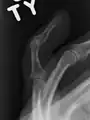

- X-ray showing fracture at the insertion of the extensor tendon

The diagnosis is generally based on symptoms and supported by X-rays.[3] The injury can be accompanied by swelling and ecchymosis.[4]

A mallet finger usually results from overbending of the finger tip.[3] Typically this occurs when a ball hits an outstretched finger and jams it.[3] This results in either a tear of the tendon or the tendon pulling off a bit of bone.[3] The diagnosis is generally based on symptoms and supported by X-rays.[3]